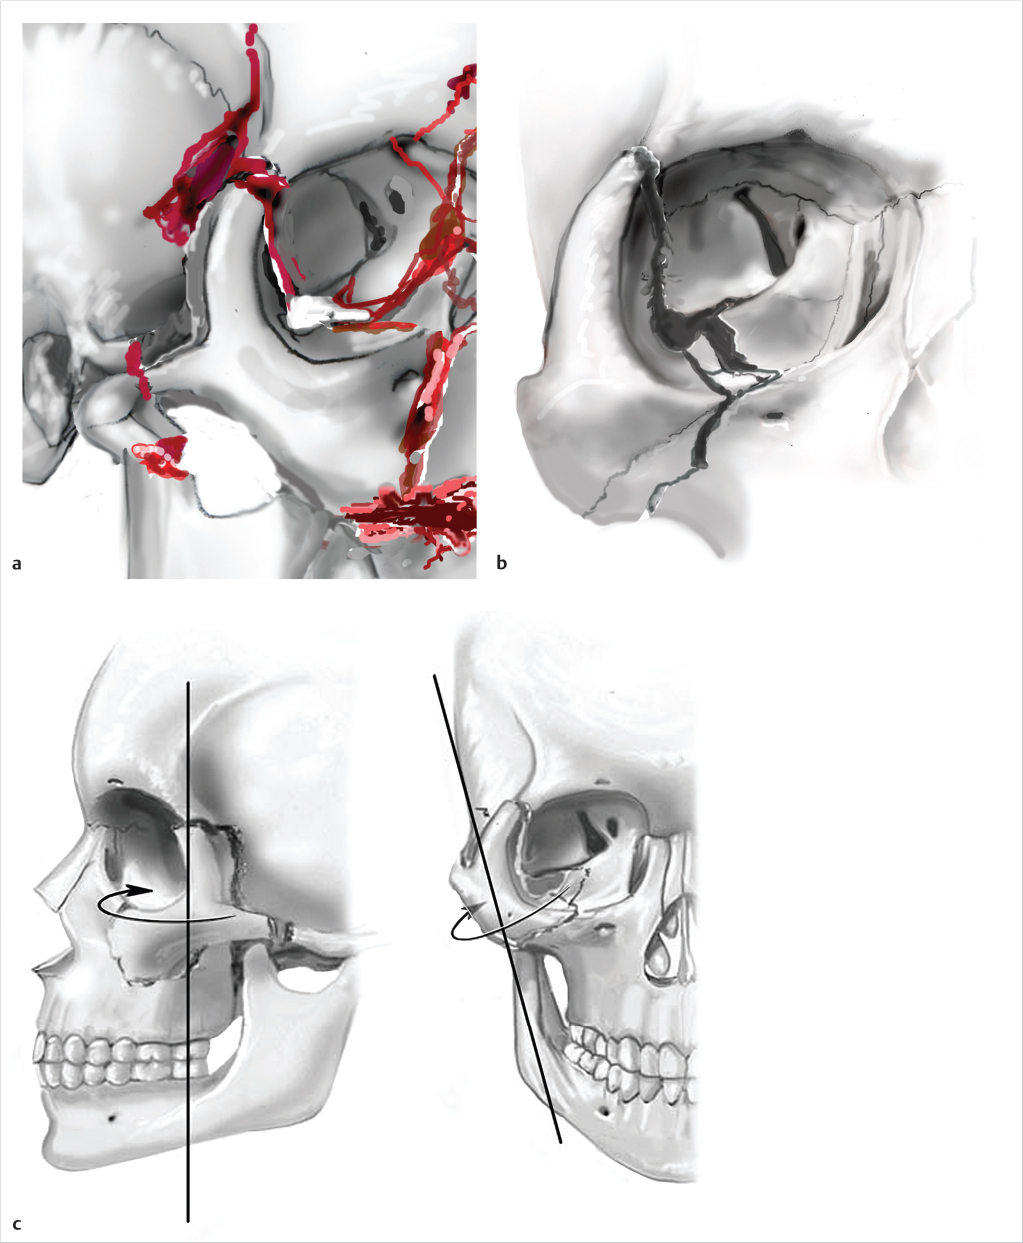

Rotation of the ZMC, in addition to displacement, creates challenges to ensure appropriate reduction. Axial rotation of the complex around any articulation may demonstrate adequate reduction at an isolated articulation, while globally the ZMC is still significantly displaced. The zygomaticosphenoid suture (ZSS) is the longest line of fracture and provides the most reliable indication of adequate reduction. The frontozygomatic suture does not reliably demonstrate adequate reduction of the ZMC due to ease of rotation of the complex around one point. Open evaluation of at least 3 points of articulation is typically recommended in significantly displaced medium and all high-energy fractures. Utilization of a Carroll-Girard screw or a Rowe elevator can be useful in mobilization of the ZMC.

While discussion of fixation is important, it should be stressed that reduction is the key to operative success. Ellis demonstrated that there was no perceptible change in ZMC position post-operatively when comparing fractures with and without fixation. 20 He suggested that post-operative asymmetry was likely secondary to unsatisfactory primary reduction. Fixation of the ZMC is primarily at the FZ and ZMB with the IOR as a secondary location for fixation. Fixation of the zygomatic arch is reserved for severely comminuted fractures or when coronal access is utilized for fixation of other fractures. The ZSS is rarely fixated. One point fixation is typically at the ZMB and two-point fixation is at the ZMB and FZ. Three or four point fixation including the IOR and ZA is reserved for significantly displaced or comminuted fractures. Should three or four point fixation be employed, orbital exploration should be considered given the high likelihood of significant floor displacement. With concomitant NOE and ZMC fractures, one must carefully consider fixation sequencing. When employing an “outside to inside” approach during treatment of multiple midface fractures, ORIF of the IOR to a laterally displaced NOE fracture can appear as an adequately reduced ZMC fracture. Significant bizygomatic widening can occur. It is the preference of the author to approach concomitant NOE and ZMC fractures medial to lateral in all but the most comminuted NOE fractures.